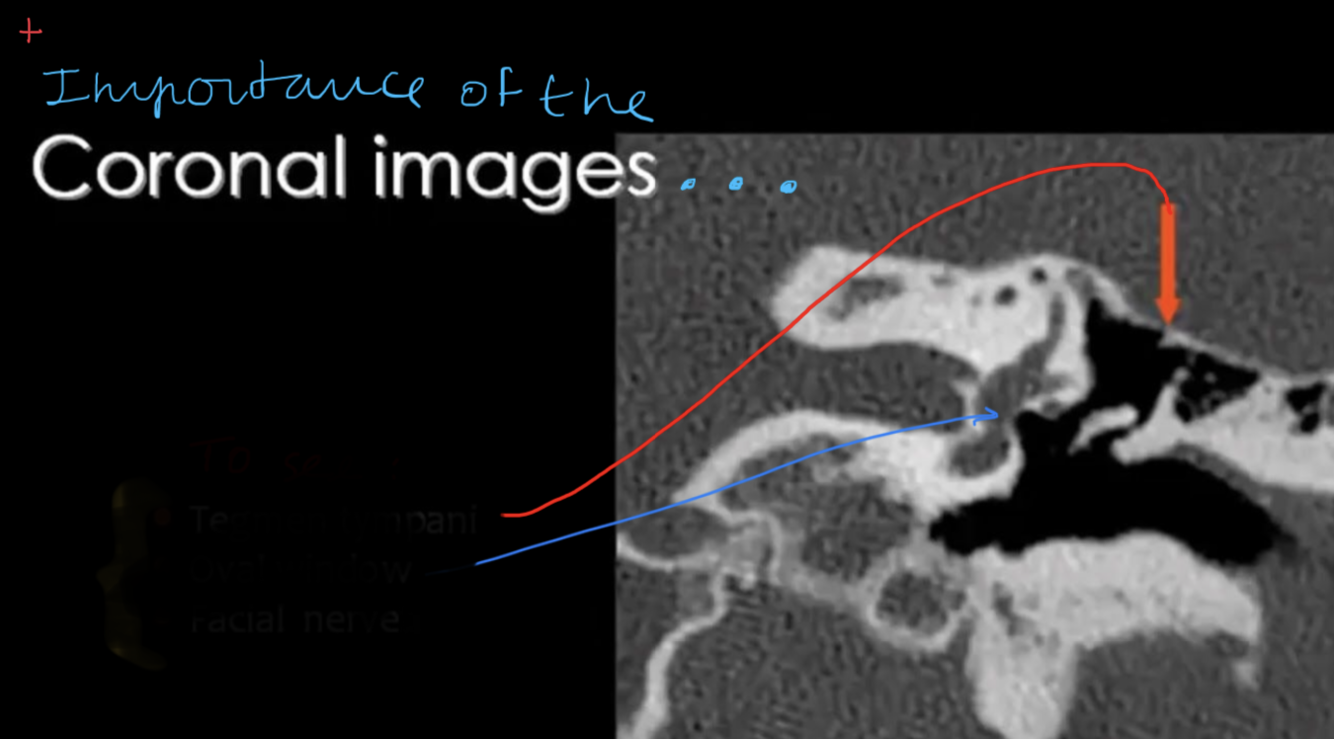

Whats the name of this line?

What is the aditus ad antrum AND mastoid antrum?

Description?